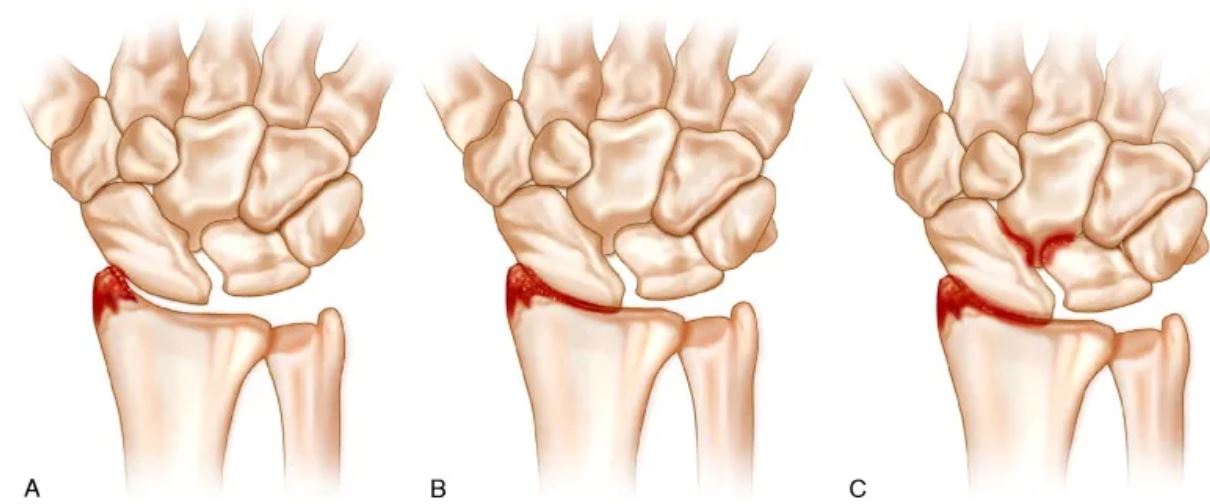

Stages of SLAC Wrist

SLAC Wrist progresses through distinct stages, which guide treatment decisions:

- Stage I: Arthritis is limited to the radioscaphoid joint, with joint space narrowing and cartilage loss on the radial side.

- Stage II: Arthritis progresses to involve the entire radioscaphoid joint.

- Stage III: Arthritis extends to the capitolunate joint, while the radiolunate joint remains relatively preserved.

- Stage IV: Advanced arthritis affects the entire wrist, including the radiolunate joint, leading to severe collapse and dysfunction.